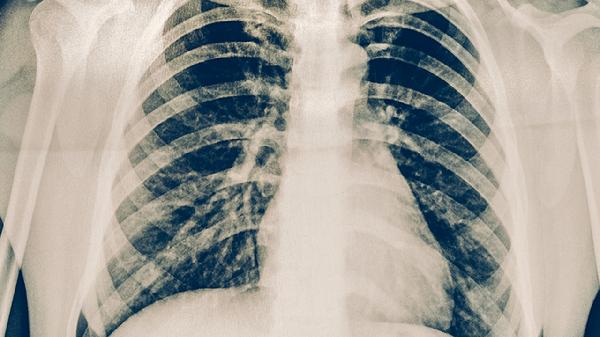

肺结核可以吃醋么 了解肺结核的饮食宜忌

肺结核患者一般可以适量吃醋,但需避免空腹或过量食用。肺结核是由结核分枝杆菌引起的慢性传染病,饮食调理需兼顾营养支持与药物相互作用,主要禁忌包括辛辣刺激、高糖高脂及影响抗结核药物吸收的食物。